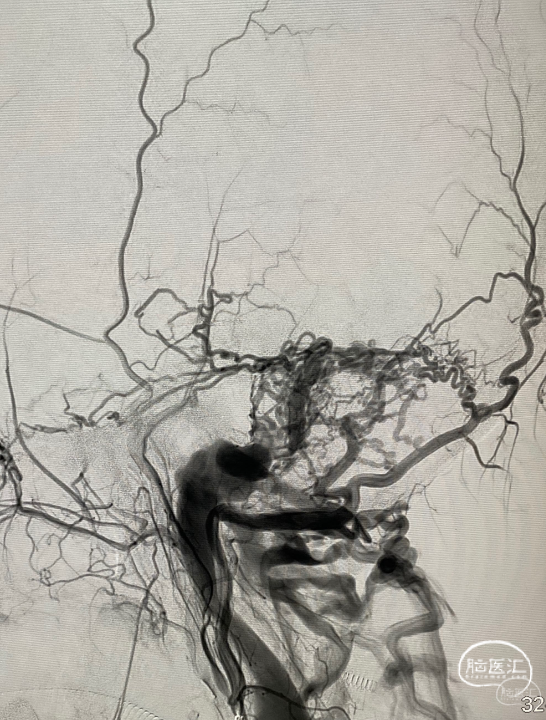

第三台,一个侧窦区的硬脑膜动静脉瘘,供血动脉繁多,以前的栓塞让脑膜中动脉的路径给用掉了。

颈内动脉脑膜垂体干有供血。

栓塞路径都不好,枕动脉供血动脉里面挑选出一支,经过努力,很好的到达了瘘口。

接着的事情就是往里面打栓塞剂。

继续打,直到将瘘口完全闭塞。

再次造影,那些繁杂的血管消失了,瘘口得到了很好的解决。